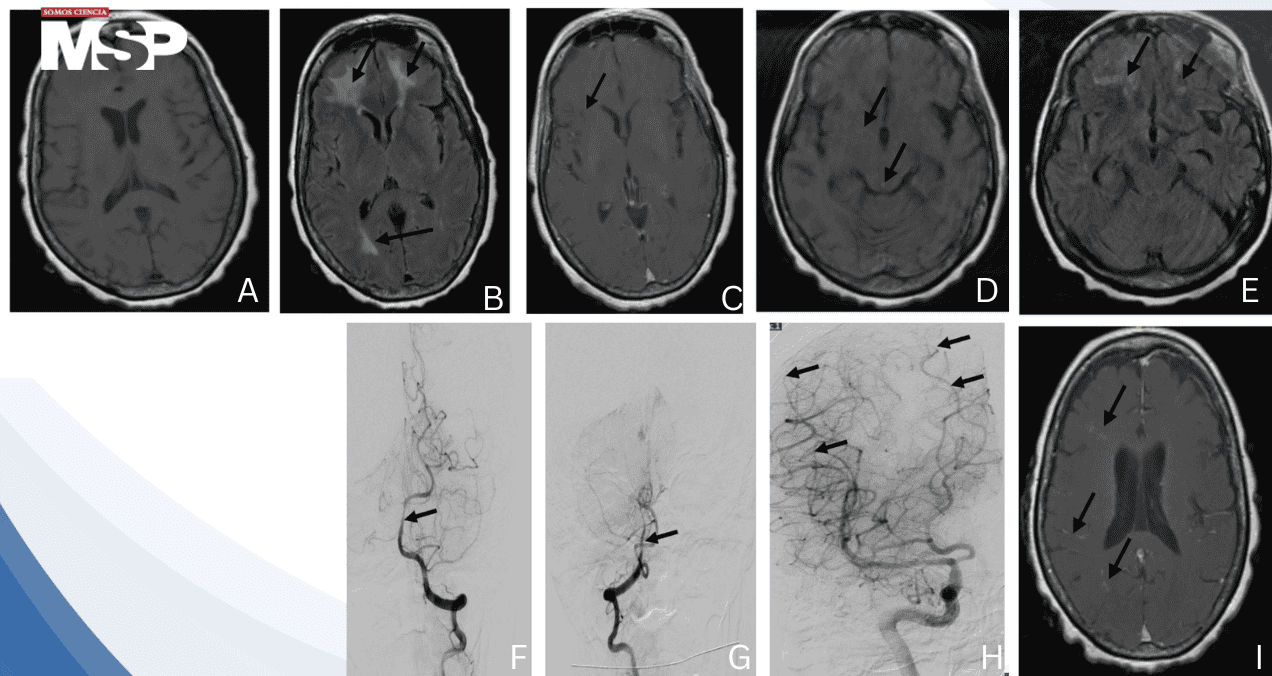

El quinto día de hospitalización, una resonancia magnética cerebral reveló hallazgos alarmantes: áreas difusas de realce de contraste en la sustancia blanca, edema vasogénico y restricción en la difusión, todo ello sugerente de vasculitis cerebral afectando los lóbulos parietal y frontal.

En esta ocasión, los cultivos fueron negativos, pero la resonancia magnética cerebral demostró progresión de la enfermedad vascular con infartos lacunares agudos dispersos, infartos cerebrales subagudos, microhemorragias y un aumento en el realce del contraste, todo ello consistente con vasculitis cerebral activa y progresiva.

La angiografía por sustracción digital confirmó el diagnóstico al demostrar irregularidades significativas de los vasos en la arteria basilar distal y en ramas medianas a pequeñas de la arteria cerebral media derecha.

Además, se identificó incidentalmente una malformación arteriovenosa cerebral. A pesar de considerar la biopsia leptomeníngea como estándar diagnóstico, la familia declinó el procedimiento dada su naturaleza invasiva y la mejoría clínica observada con el tratamiento.